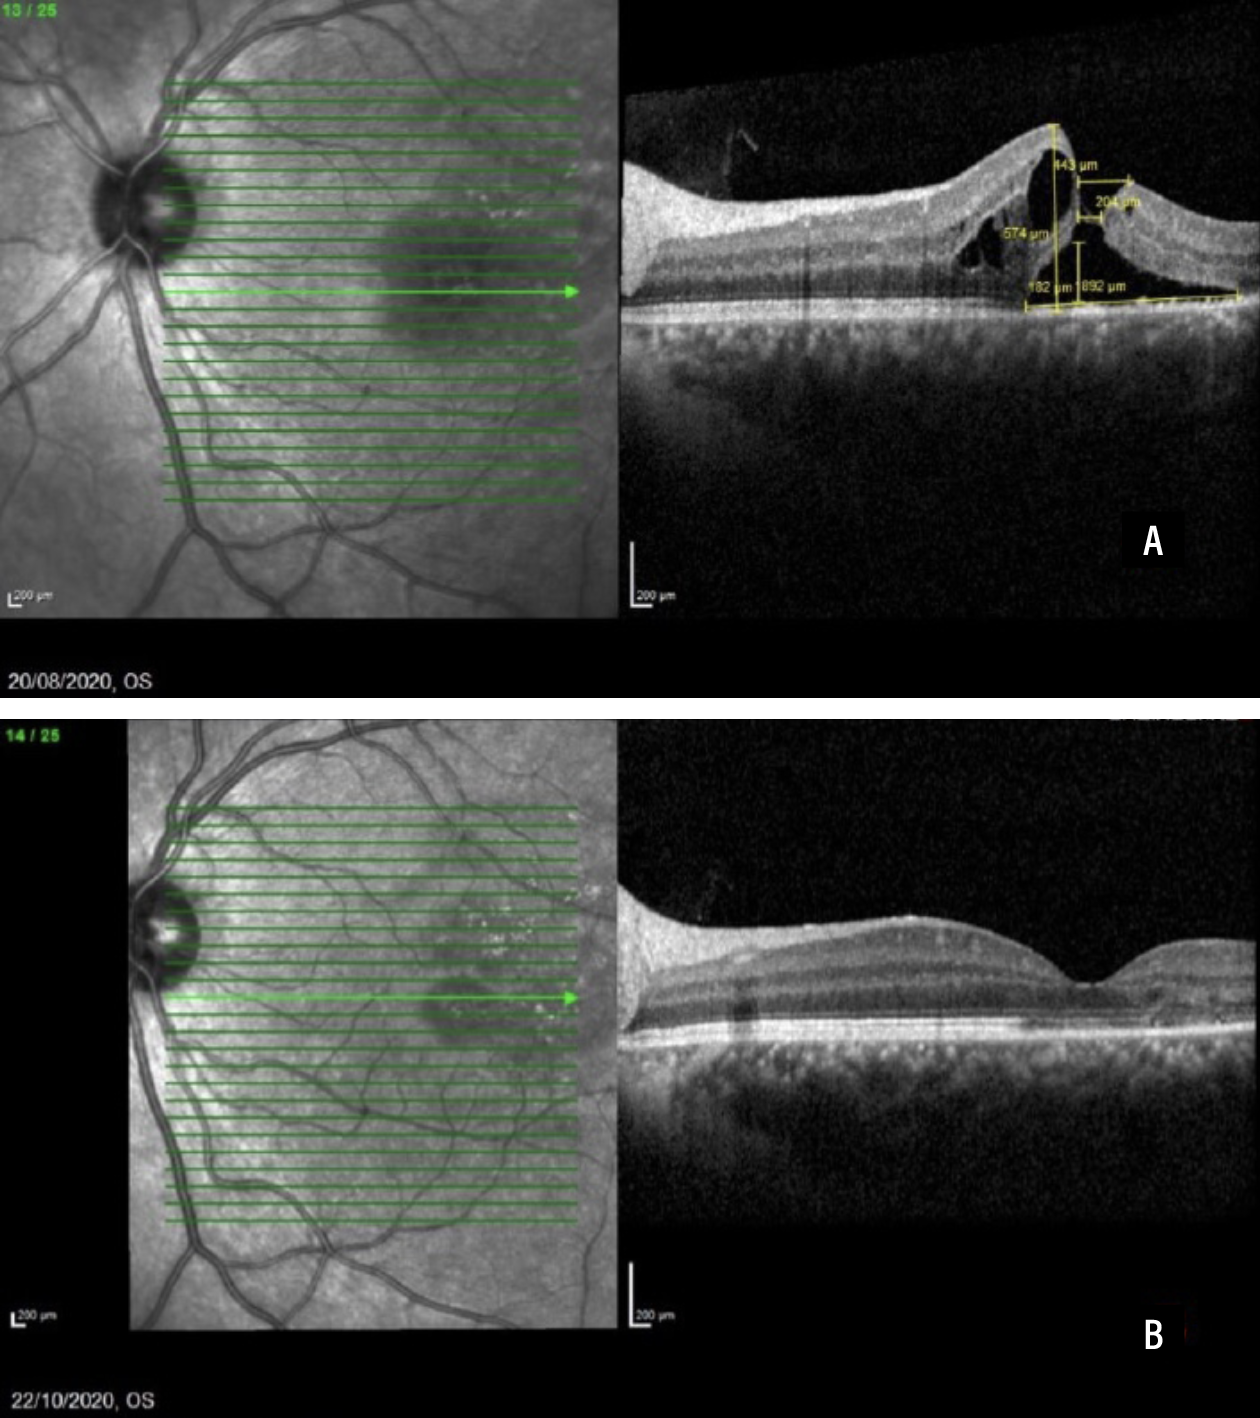

Figure 2 shows a case of a patient that had sustained a sports-related injury and started on topical NSAIDs, with hole closure resulting in visual acuity improvement from 20/40 to 20/20.

| Figure 2. Spectral-domain optical coherence scans before full-thickness macular hole closure (A) and two months after closure (B). This 24-year-old White male sustained a sports injury and was started on topical NSAID. Visual acuity improved from 6/12 (20/40) to 6/6 (20/20). (Reprinted with permission from Uwaydat SH, Mansour A, Ascaso FJ, et al. Clinical characteristics of full thickness macular holes that closed without surgery. Br J Ophthalmol. 2022;106:1463–1468.)3 |